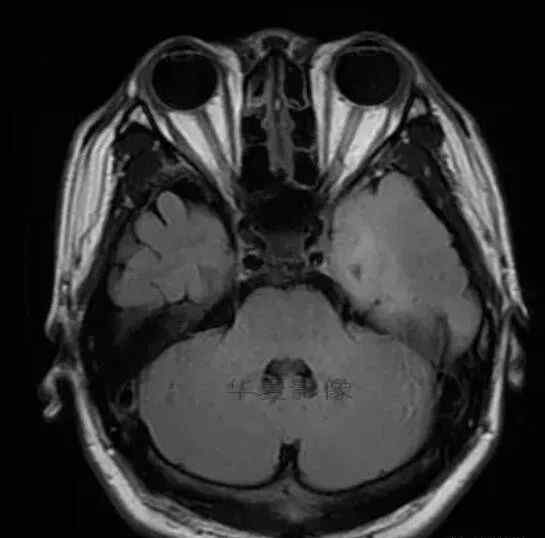

1.左侧颞叶、海马和岛叶T1WI信号低,T2WI信号高

2.病变没有明显的边界

3.占用效果不明显

4.豆状核不受影响